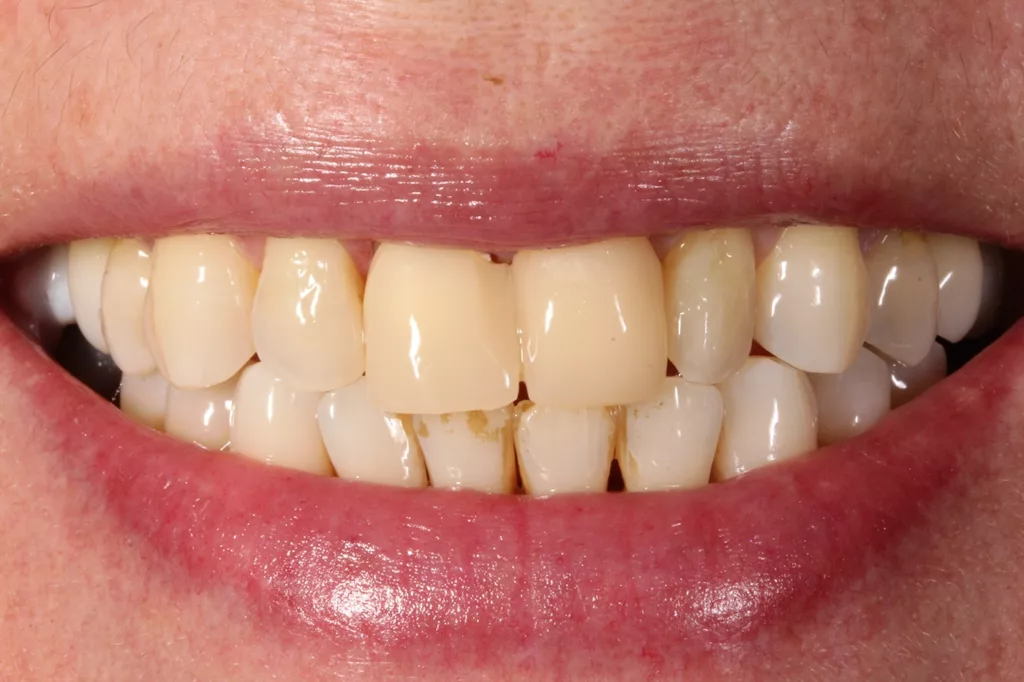

Das Finishing der Feinstruktur-Feldspatkeramik erfolgte wie im ersten Patientenfall. Nach Einprobe und Eingliederung mit einem selbstadhäsiven Befestigungskomposit (Panavia, Kuraray Noritake) zeigte sich ein restauratives Ergebnis, das von den natürlichen Zähnen nicht zu unterscheiden war (Abb. 11 und 12).